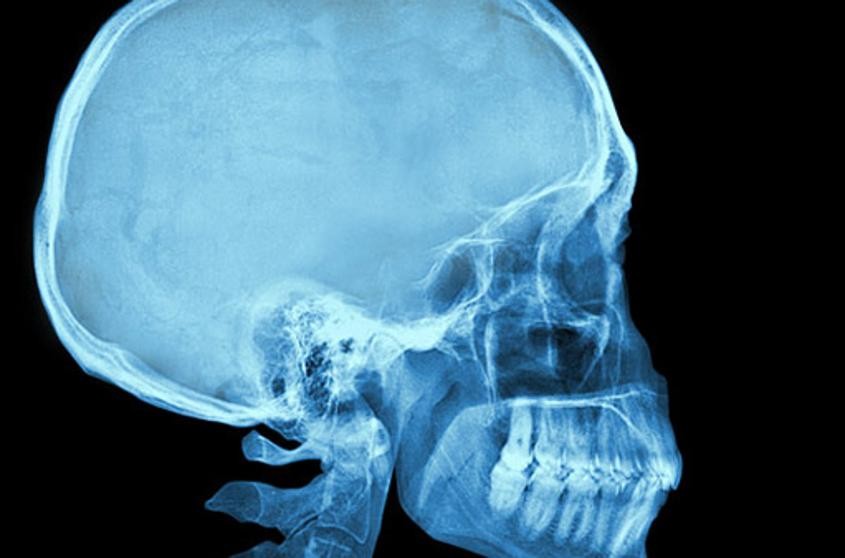

Una menor india, que padecía fuertes dolores de cabeza y convulsiones epilépticas desde hace seis meses, llevaba 100 huevos del parásito conocido como tenia en su cerebro, descubrieron los médicos de un hospital.

De acuerdo con India Today, al escanear su cerebro los médicos descubrieron 100 quistes que en realidad eran huevos del parásito y que habían migrado desde su estómago.

La existencia de esos quistes causó inflamación en su cerebro, así como problemas a la hora de respirar y caminar. La menor fue hospitalizada ya casi inconsciente, precisan los especialistas.